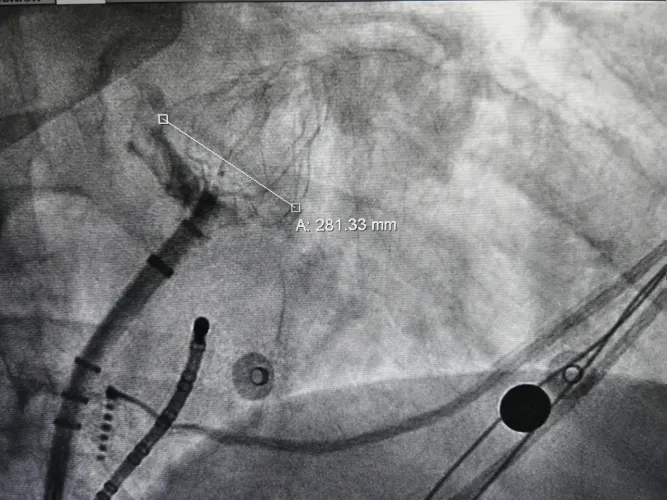

DSA造影复测缺损

右肩位:RAO 30° +CRAN 20°

肝位:RAO 30° +CAU 20°

术中肝位测量:

心耳开口直径:24.9mm

心耳深度:26.9mm